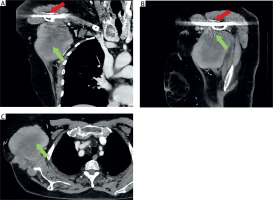

A 71-year-old woman was referred to our department due to the presence of a lesion in the right chest wall, arising from the axillary cavity, which had been increasing in size during the last 3 years. She had a history of metabolic disorders and surgical osteosynthesis of the right shoulder 4 years before, with the presence of titanium plate. Physical examination revealed a swelling approximately 10 cm in size on the right chest wall, firm and fixed to the underlying layers. This was associated with functional limitation of the right arm due to pain and mechanical limitation. The computed tomography (CT) scan with contrast showed a solid nodular mass in the right axillary cavity with finely irregular margins, heterogeneous contrast enhancement, and dimensions of approximately 10.5 × 8.3 cm (Figure 1).

Figure 1

Preoperative radiological imaging of a mass located in the right axillary cavity. A – Coronal section of computed tomography (CT) demonstrating the presence of the mass (green arrow) and a titanium plate in the shoulder (red arrow). B – Sagittal CT section highlighting the close anatomical correlation between the mass (green arrow) and the titanium plate (red arrow). C – Image of the lesion through an axial CT section (green arrow)